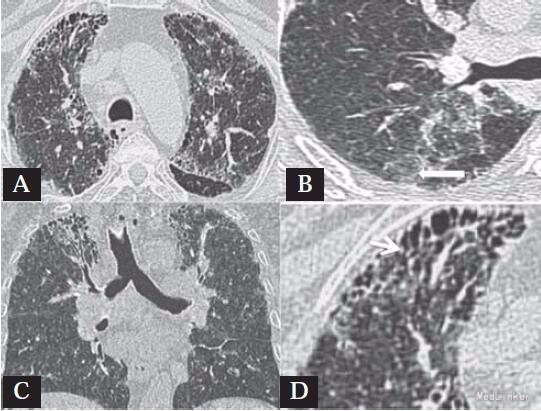

查体:杵状指,双肺吸气末捻发音。余未查见特殊。 辅查:血常规、肝肾功均正常。锻炼前后(步行实验)氧饱和度和脉搏分别为95/88和89/98,超声心动图提示I级舒张功能不全,左室射血分数为55%,肺动脉压为25mmHg,肺功能提示混合性障碍,FVC为2.36(预计值为69%),FEV1为1.63(预计值为56%),FEV1/ FVC比为68,胸片提示双肺网状影(图1),高分辨率CT(HRCT)提示小叶间隔增厚及蜂窝状影(图2). 支气管肺活检显示间质性纤维化伴炎性浸润,有慢性炎细胞浸润。炎性细胞间的巨噬细胞充满色素,普鲁士蓝铁特殊染色为阳性,提示铁末沉着病(图3)。

随访:一年后随访患者肺功能FEV1和FVC下降,HRCT无显著恶化。 讨论:肺铁末沉着病常见于电焊工人,其他也有患此病风险的是开采和加工铁矿石、钢铁轧钢厂、铸造工人。该病尚未报道见于车床工人。目前HRCT是诊断间质性肺病的推荐检查,常常表现为磨玻璃样影。组织病理学发现纤维化肺泡隔间有铁质沉着为诊断标准。暴露于铁尘是不管是在吸烟还是非吸烟患者都是引起阻塞性肺功能不全的危险因素。因此该患者阻塞性肺功能异常可能是吸烟和暴露于铁尘造成的。吸烟可能通过破坏呼吸上皮降低肺去除灰尘 的能力。另外,通过在工作场所吸烟吸越深,吸烟者可吸入比不吸烟者更多的灰尘。从而, 吸烟可能加重了铁末沉着。该病例提醒临床医生必须对有潜在的职业暴露引起的间质性肺疾病保持高度的怀疑和获得一个完整的职业状况。 引自[Interstitial Lung Disease due to Siderosis in a Lathe Machine Worker]